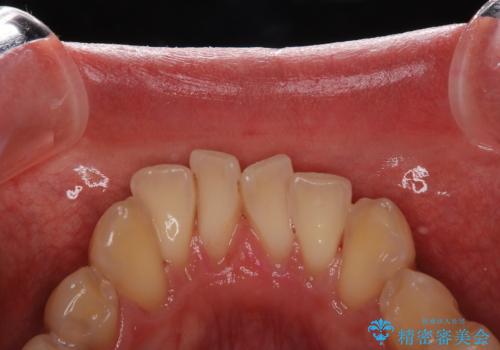

セラミックを付ける前にエアフローで綺麗ににクリーニング

- セラミックの詰め物を付ける前に、全体のクリーニングを希望とのことでした。

染め出しをし、歯磨き指導とクリーニング(エアフロー60分コース)を行いました。